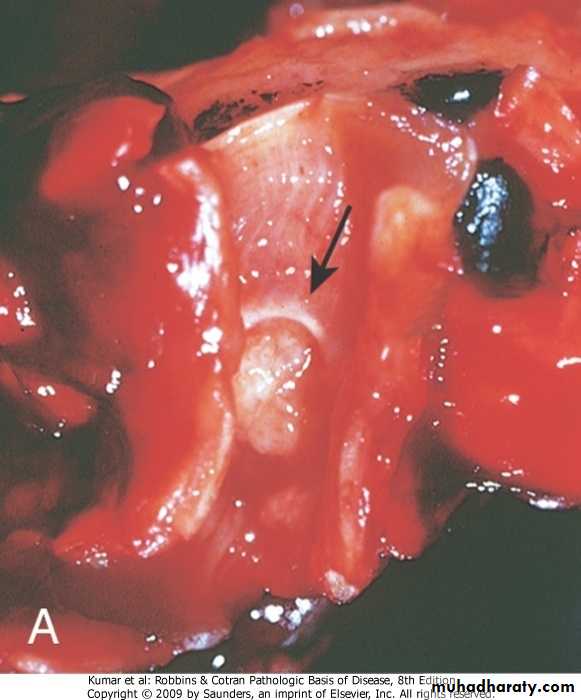

Sequence of changes in bronchial epithelium

Clinical evidence:obtained from observation of histological changes in bronchial epithelium in smokers . There is sequential changes leading to squamous cell carcinomaPathology of bronchogenic carcinoma

Histopathological classification:1. Squamous cell carcinoma ; arises from squamous metaplastic epithelium---dysplasia---carcinoma in situ---invasive carcinoma.

It is usually poorly differentiated

Squamous cell carcinoma of bronchus